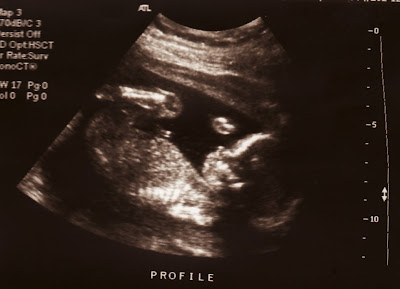

So there we were, Friday, decker is ready to go, the car is packedfor the cottage and then we go in for our ultrasound, of which paul has only seen the baby at 8 weeks as a blob with a little heartbeat, so this was a big thing for paul too.

So during the ultrasound the baby looks huge to me HUGE, I ask how big it is measuring now (almost 13 cm from head to bum, plus legs, it was 6 cm the last time I saw it at 12 weeks, during the ultrasound we were measuring around 19 weeks). The baby is moving just slightly and we can see so much more than last time, which includes but not limited to :

a heart with 4 healthy valves

kidneys

stomach

ribcage

spine

brain hemispheres

femur

5 toes

5 fingers

and swallowing (paul was most excited by this as the baby seemed very content to just chill out for the time being)

After the required measurements are taken, she asks if we would like to know the gender, YES, TELL ME NOW. please. She says she doesn't know yet, but will look now for us. Paul and I hold our breaths, ready and she says "There is what could be a penis or a large part of the vagina." (pardon my use of the v and p word if it offends). WHAT?

Then the baby crosses its legs, sitting and crosslegged up in there for the next 15 minutes while she wholeheartedly tries to see for us BOY or GIRL? She can see that the baby is not moving, and is quite content, she tries some different angles, but eventually she has to say "The sac (pardon) has not yet dropped, so i can only say that I am 80% sure it is a BOY".

So that is it folks, we're 80% sure it is a boy, and 100% sure that everything is amazingly healthy and for that we could not be more thankful. And we'll be stocking up on some white sleepers (it will be august anyways when we know for sure for sure) And buying up boy clothes, but leaving tags and receipts with them, just in case.